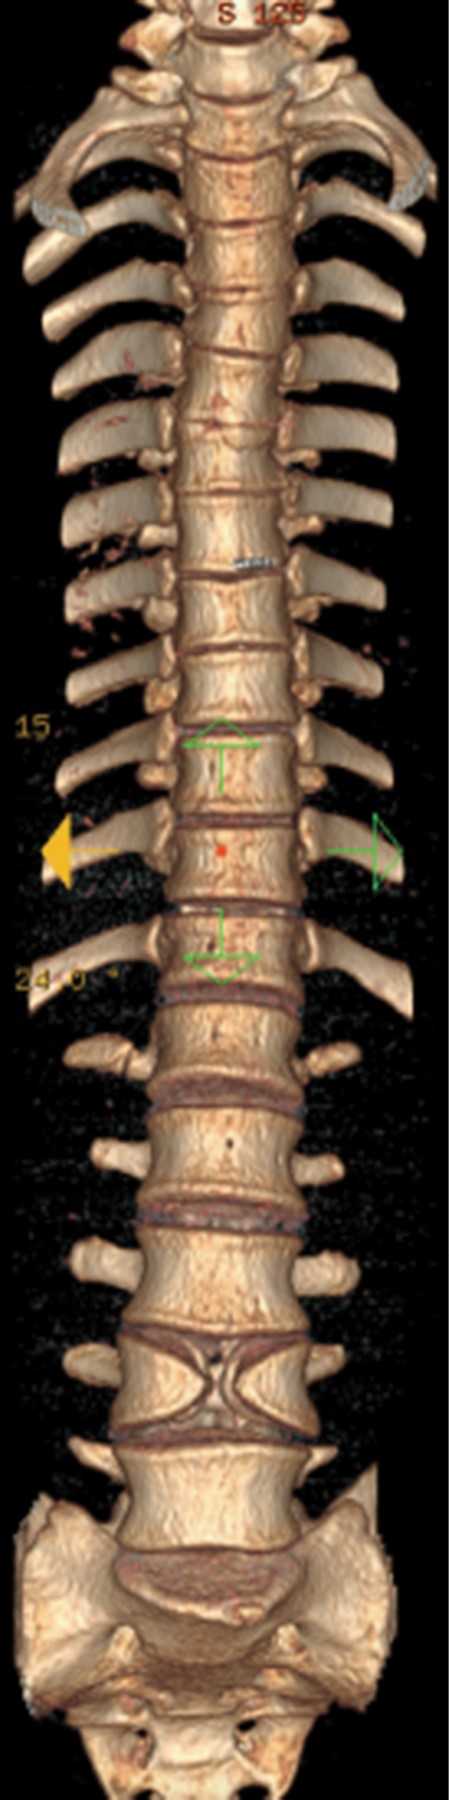

Se realizó tomografía de columna lumbar en cortes sagital, coronal y axial, así como reconstrucción en 3D, donde se identificaron lesiones en alas de mariposa y también se reconoció afectación en cuerpos vertebrales de T5-T6 y T12 (Figuras 3, 4, 5 y 6).